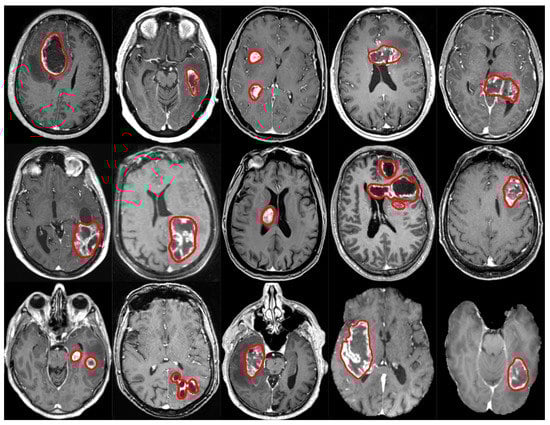

5.2. Architecture Comparison

| Arch. | Pixelwise | Patientwise (PW) | |||||

|---|---|---|---|---|---|---|---|

| Dice | Dice-TP | HD95 | FPPP | F1 | Recall | Precision | |

| HNF-Net | - | - | - | - | - | ||

| nnU-Net | |||||||

| AGU-Net | |||||||